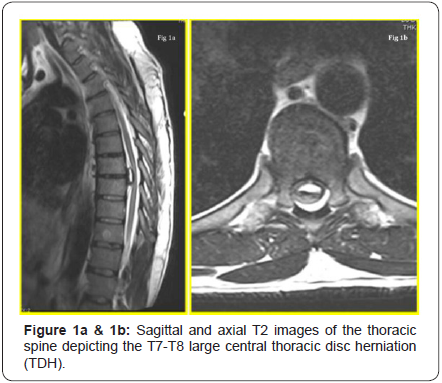

A working diagnosis of a potential space occupying lesion (SOL) in the thoracic region, causing mechanical compression of the spinal cord and/or nerve root(s), was suspected. An immediate MRI scan was arranged, which revealed a large mass causing the ventral effacement of CSF flow / signal at the T7- T8 level. His T2 weighted MRI images are illustrated in (Figure 1a & 1b). The differential diagnosis included disc herniation and other benign intra-axial neoplasms (i.e. meningioma and schwannoma). A CT scan was requested to further understand the lesion, study the extent of calcification / bony, and the intradural involvement (if any). The key CT sagittal and axial images are depicted in (Figure 2a & 2b). From these, the diagnosis narrowed down to a large central calcified TDH, following a discussion at the multi-disciplinary team (MDT) meeting.

He was seen in the pre-assessment clinic two weeks prior to the scheduled surgical date, reporting spontaneous improvement in his back pain and anterior-chest band like tightness, and with a resolution of his lower extremity tingling/numbness. His ODI was 4%. The proposed surgery was withheld and an interval MRI scan of his thoracic spine was requested. The T2 weighted images at two months from his initial MRI revealed the regression of the large central calcified TDH and this is illustrated in (Figure 3a & 3b). He had a complete resolution of his symptoms while waiting for surgery and he had normal neurology.He signed a written consent form and permitted us to submit and publish his clinical course of events as a case report provided he remained anonymous.